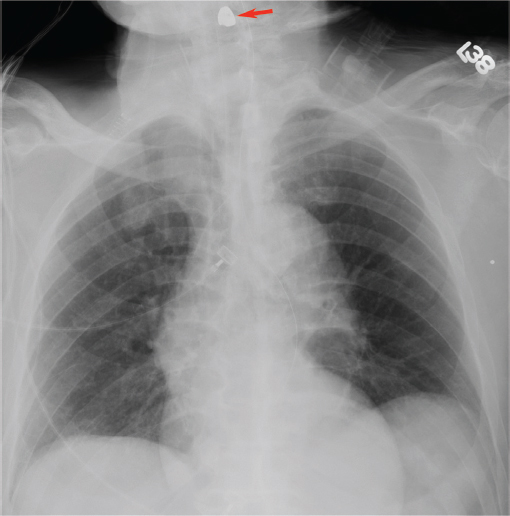

Preoperative occlusal evaluation should be performed by having the patient bite down into his or her best fit occlusion. Careful examination of the dentition will identify loose or avulsed teeth. If teeth are missing, chest imaging should be performed to ensure that they have not become airway foreign bodies ( Fig. 65.3 ). Fig. 65.4 demonstrates variants of adult occlusion. Ideal occlusion or Angle’s Class I occlusion occurs when the mesialbuccal cusp of the maxillary first molar rests in the buccal groove of the mandibular first molar ( Fig. 65.4a). Class II occlusion occurs when the mesialbuccal cusp rests anterior to the buccal groove. There are two divisions of Class II occlusion. In the first division ( Fig. 65.4b ), the incisors demonstrate an overjet. In the second division, the incisors are palatally tilted to compensate for the abnormal occlusion; this results in a more normal appearing dental relationship anteriorly ( Fig. 65.4c ). Class III occlusion occurs when the mesialbuccal cusp rests posterior to the buccal groove ( Fig. 65.4d ). 12 Wear facets on the teeth may offer hints to the preinjury occlusion in patients with poor dentition or longstanding malocclusion. An anterior open bite suggests possible subcondylar fracture(s). Grasping and attempting to manipulate the fractured mandible segment may assist in assessing instability of the fractured segment. Bilateral fractures may result in an unstable central mandible fragment that when posteriorly displaced results in tongue prolapse and airway obstruction. Anterior traction on the tongue with a heavy suture or towel clamp can restore and maintain the airway acutely while deciding on more definitive airway management such as intubation or tracheotomy. 13